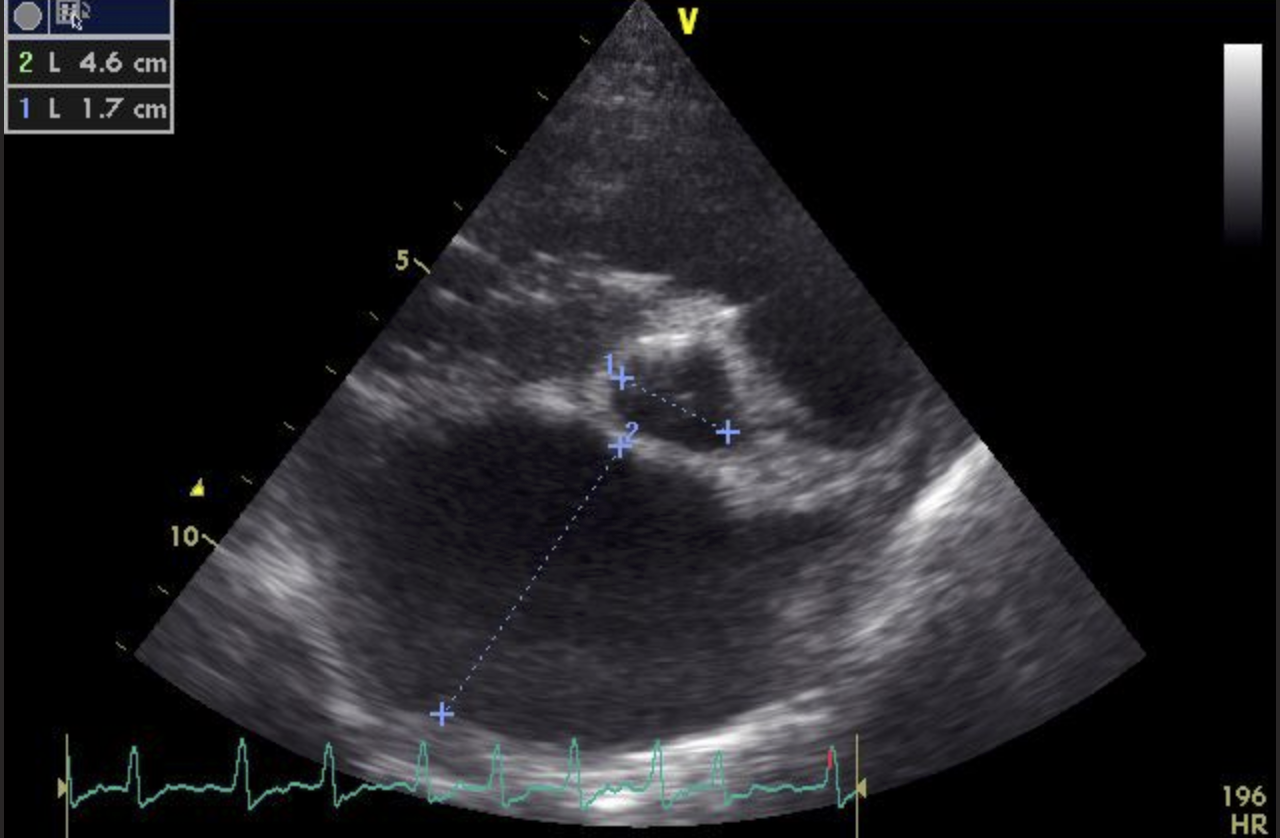

Die Ultraschalluntersuchung des Herzens zeigt letztendlich die Ursache der Veränderungen: Bubbles Herzklappe zwischen dem linken Vorhof und der linken Herzkammer, die Mitralklappe, schließt sich nicht mehr vollständig. Das EKG bei Bubbles ist in Ruhe unauffällig.